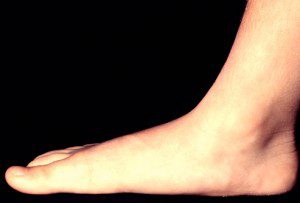

از بین رفتن انحناء کف پا که از تماس کامل یا نزدیک به کامل با زمین مشخص می شود. این ممکن است ارثی باشد یا ناشی از یک صدمه یا شرایطی مانند : آرتریت روماتوئید ایجاد شود.

علائم از بین رفتن انحناء کف پا نادر است . افزایش وزن، کفش بد و یا ایستادن بیش از حد ممکن است باعث درد شود. درمان شامل تمرینات تقویتی پا و کفش با پشتیبانی از قوس خوب می باشد.